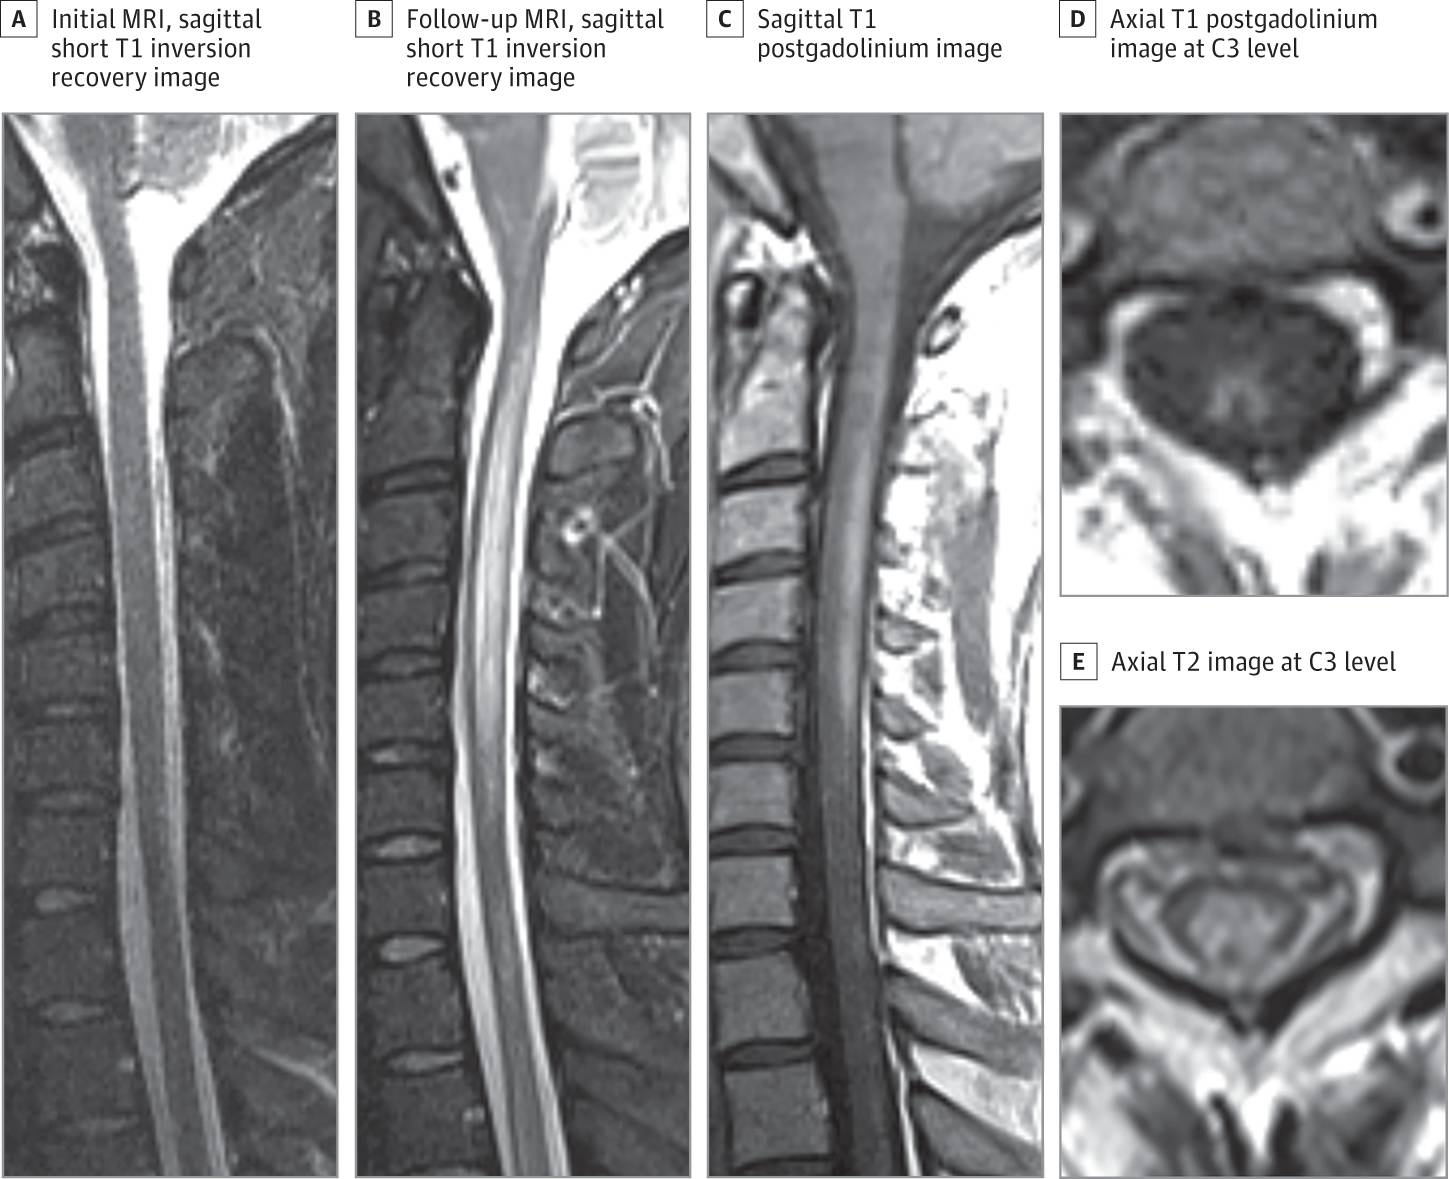

30岁男性,既往体健,因肢体感觉异常伴运动不协调就诊。症状出现后5周患者行脊髓MRI检查,未见明显异常(图A)。随后的8周,患者逐渐出现躯干束带感及明显的感觉性共济失调。患者至神经科求进一步诊治。神经系统查体远端肢体肌力4+级,下肢重于上肢,下肢振动觉和本体觉消失,而上肢远端振动觉和本体觉明显减退。通过针刺觉及温度觉测试未发现明确的脊髓感觉平面。跟膝胫试验和指鼻试验欠稳准,前者更突出。Romberg征阳性。上肢深腱反射2+,下肢深腱反射3+。右侧病理征阳性。住院5天,患者因严重的感觉性共济失调无法自主行走或站立。

起病13周后再次复查MRI提示C2-T9长节段脊髓脱髓鞘病灶,从脊髓中央灰质延伸至前角细胞以及背柱(图B,E)。注射对比剂后可见多个层面强化(图C,D)。维生素B12水平187pg/mL(如转换为pmol/L,需×0.7378),甲基丙二酸水平3166U/L。内因子和胃壁细胞抗体检测阴性。进一步排除了其他脊髓病的常见原因:HIV和视神经脊髓炎抗体阴性,RPR阴性,锌和铜水平正常。脑脊液细胞计数,蛋白和糖水平正常;未见寡克隆带;VDRL检测阴性。追问病史,患者诉过去的一年曾使用一氧化二氮娱乐,每天吸入多达100罐的一氧化二氮。

(A:起病5周时的MRI;B-E:起病13周时的MRI)

长节段脊髓脱髓鞘可见于一氧化二氮脊髓病和其他类型的亚急性联合变性,但近乎全脊髓长度受累的病例尚未见报道。病灶强化不常见或仅有轻度强化。本例如此广泛明显的脊髓强化病灶还是第一次见到。亚急性联合变性常可见T2高信号的倒V字征(inverted V sign),而本例首次报道了强化的倒V字征(图D)。如此严重且不同寻常的影像学特点增加了初步诊断的难度,我们不得不担心患者长期的预后问题。给予维生素B12补充并停用一氧化二氮后,患者症状戏剧性好转,1年后神经系统功能缺失症状消失。